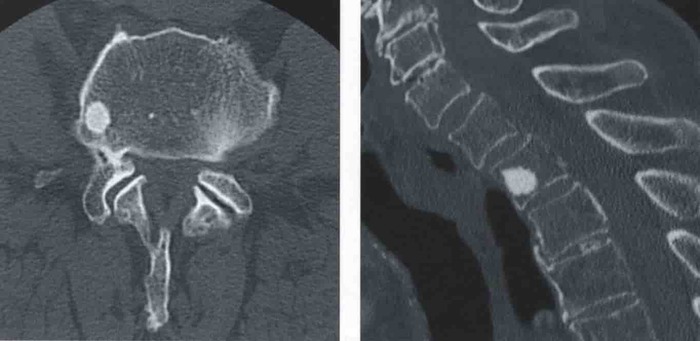

КТ

Варианты эностозов на КТ И МРТ.

Эностоз лечения не требует, динамическое наблюдение за его размером, ростом/его отсутствием.

Категория годности с диагнозом эностоз-по ст.10(Доброкачественные новообразования (кроме доброкачественных новообразований нервной системы и мозговых оболочек), новообразования in situ:),в) при наличии объективных данных без нарушения функции- А2-годен к военной службе.